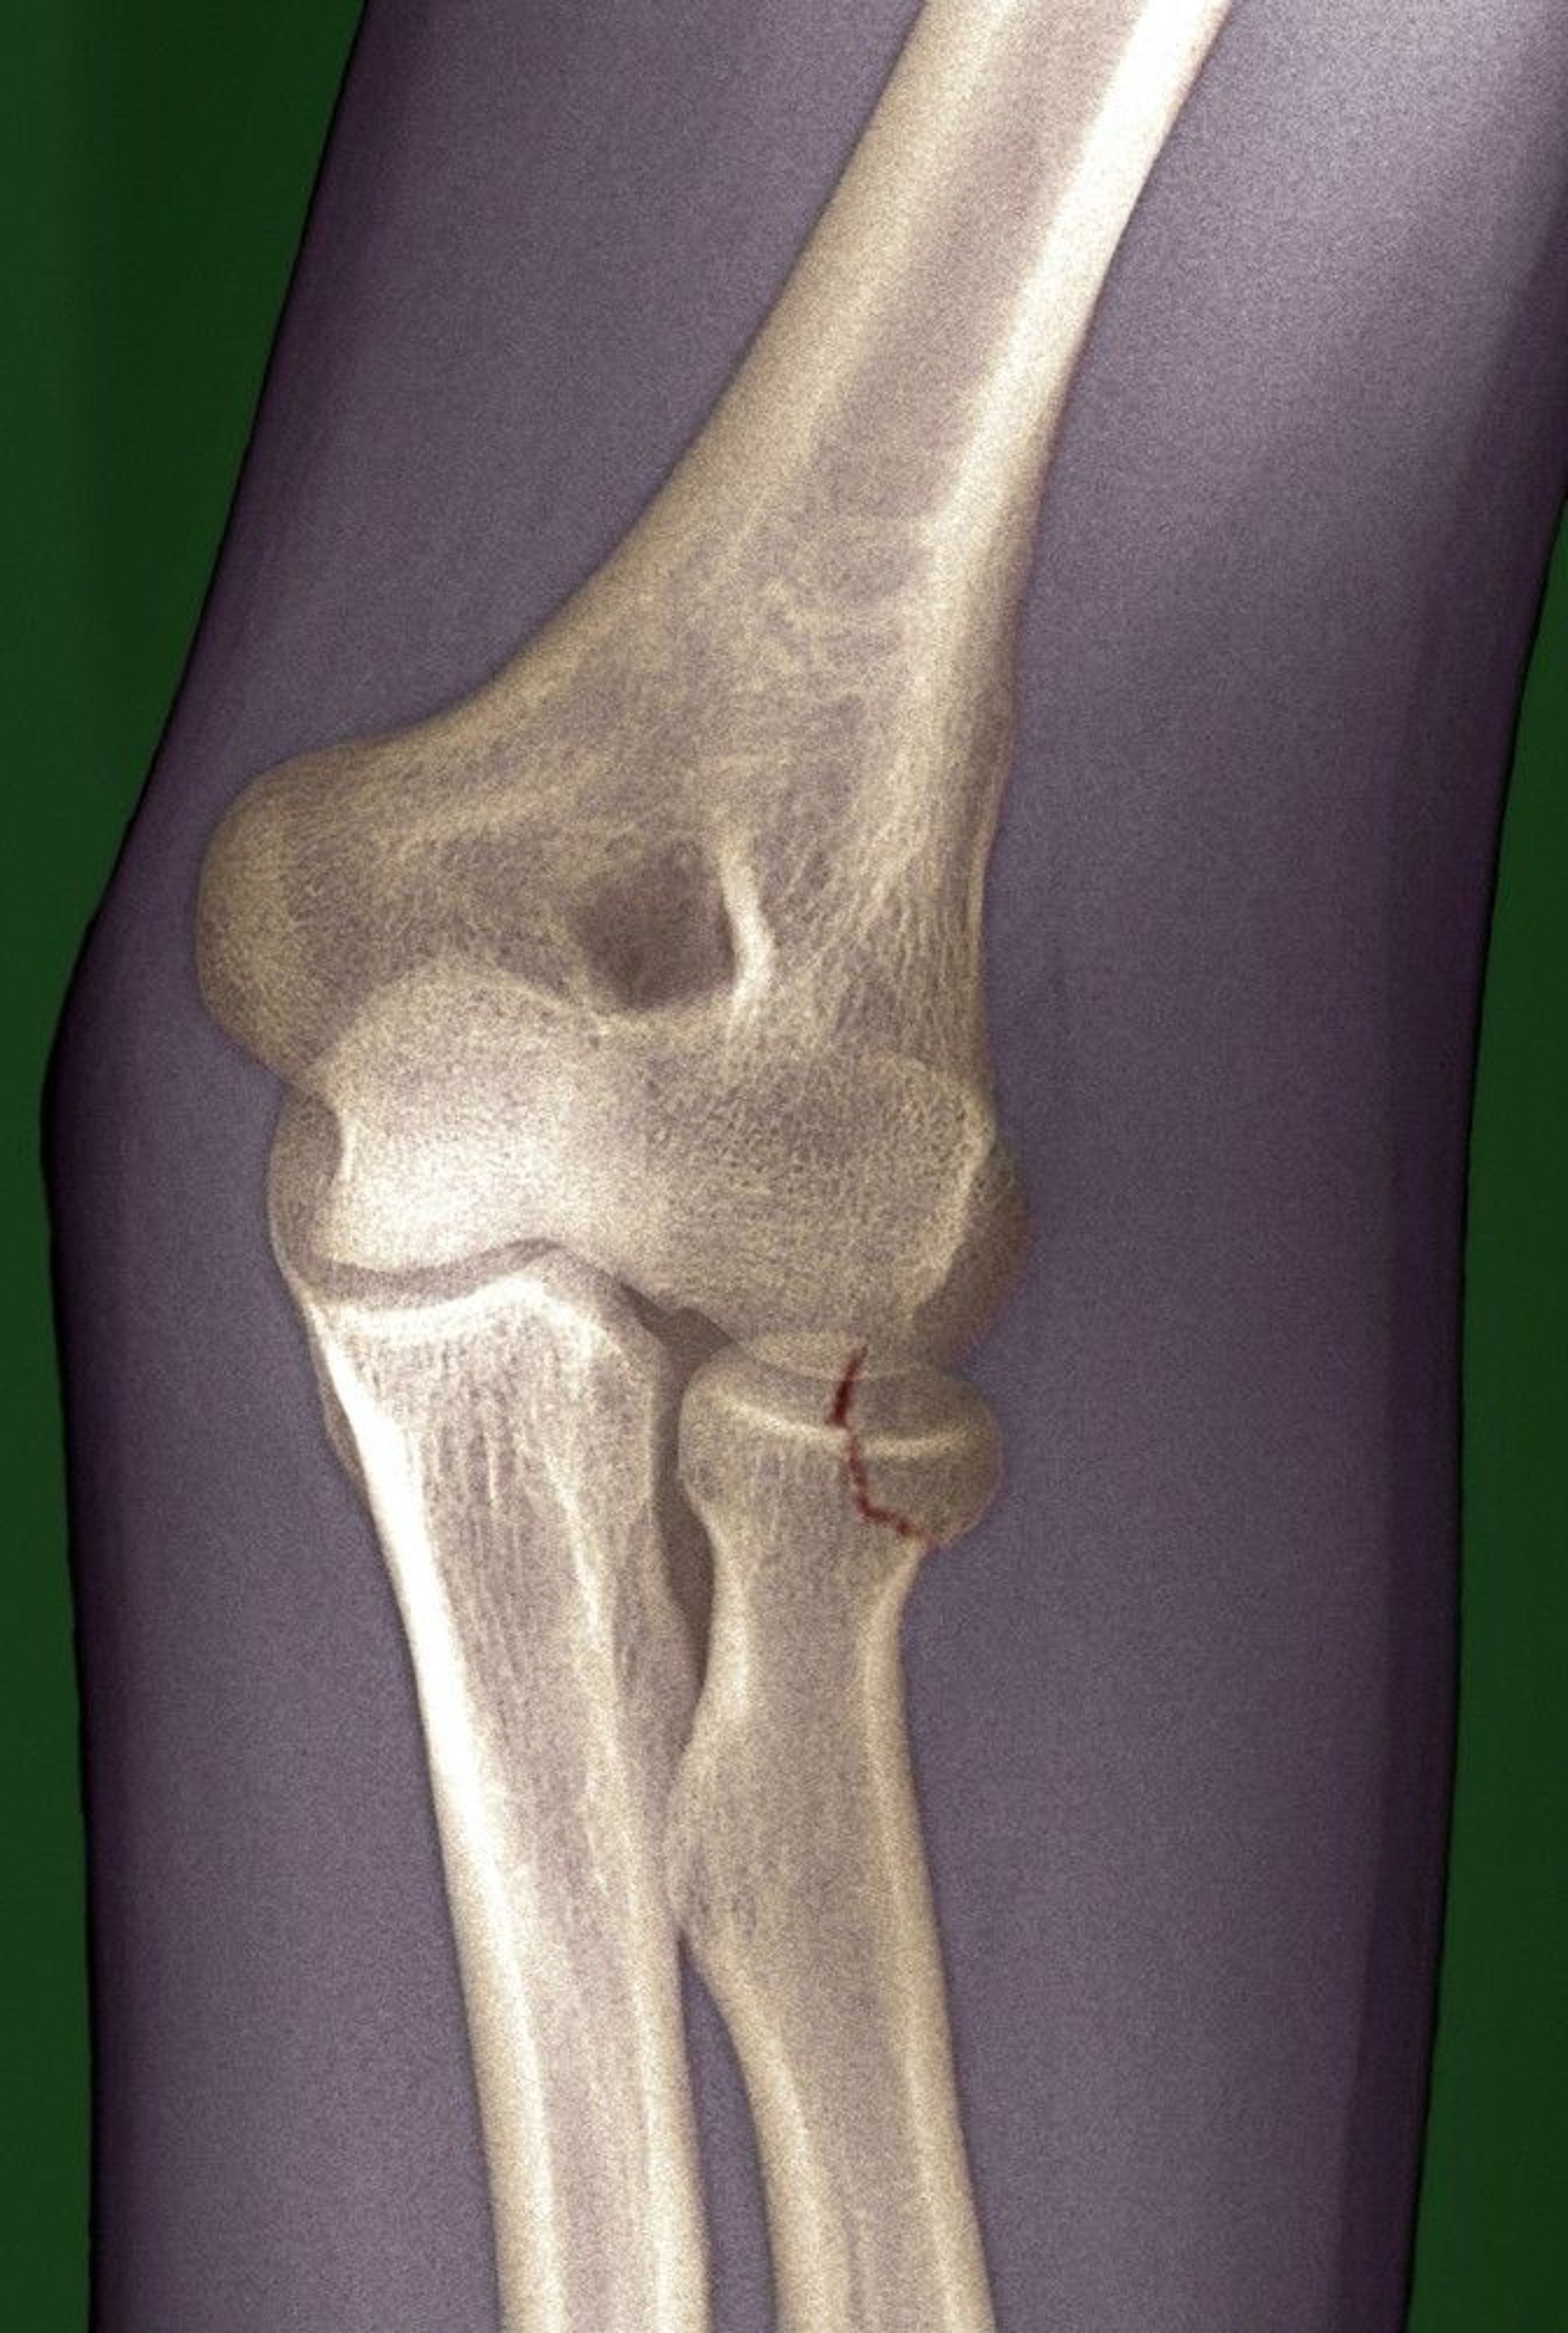

Radial Head Fracture

The fracture line (marked in red here) is subtle and could be easily missed.

DU CANE MEDICAL IMAGING LTD/SCIENCE PHOTO LIBRARY